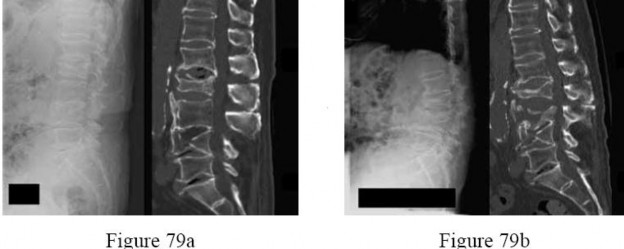

Question 29:

Distraction osteogenesis, as pioneered by Ilizarov, is a powerful technique for limb lengthening and deformity correction. The formation of new bone across the distraction gap primarily relies on which biological process?

Correct Answer: Intramembranous ossification

Explanation:

Distraction osteogenesis relies primarily on intramembranous ossification. Under conditions of stable fixation and controlled, gradual distraction (typically 1 mm per day), osteoblasts directly deposit osteoid along the collagen bundles in the distraction gap without a cartilaginous intermediate. Endochondral ossification (bone formation via a cartilage model) is typical of secondary fracture healing with relative stability.